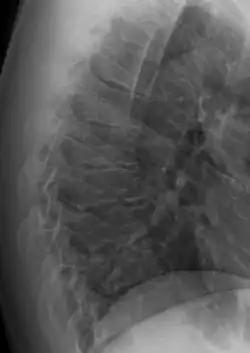

Scheuermann's disease on lateral Xray of the T spine